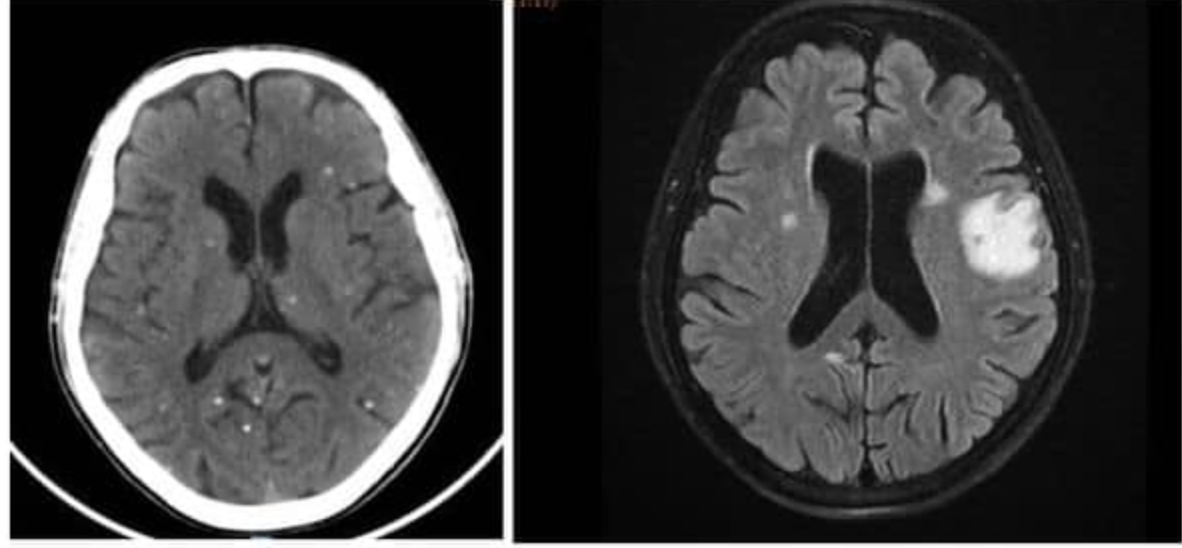

Sau khi được thăm khám lâm sàng, bệnh nhân được chụp cộng hưởng từ (MRI) sọ não ghi nhận tổn thương não nhiều vị trí, phù não. Bác sĩ nghi ngờ bệnh nhân nhiễm ký sinh trùng ở não nên tiếp tục thực hiện xét nghiệm huyết thanh học xác nhận kết quả dương tính với ấu trùng sán dải lợn Cysticercus.

Bệnh nhân được chụp Xquang xương đùi, CT-scan ngực để tầm soát tổn thương ở cơ quan khác, phát hiện vô số nang sán dải còn sống hoặc đã bị hóa vôi "ẩn nấp" trong não, nhu mô phổi, và trong da, cơ trên toàn bộ cơ thể người bệnh.

Trường hợp này được chẩn đoán viêm não do nang sán dải lợn và nhiễm nang sán dải ở đa cơ quan, nổi bật nhất là ở não, mô dưới da và ở cơ. Người bệnh nhanh chóng được điều trị bằng thuốc chống ký sinh trùng, chống viêm, phòng ngừa co giật cùng với chăm sóc tích cực. May mắn, bệnh nhân hồi phục tốt sau quá trình điều trị và được xuất viện.